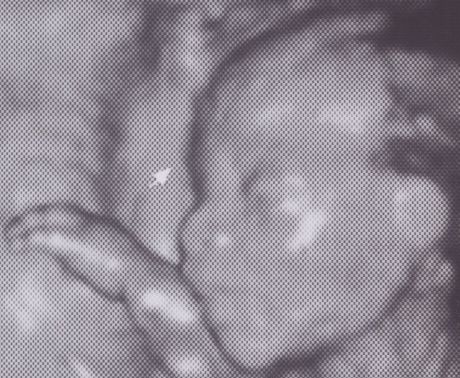

2007-07-07 16W3D 體重 - 153 g

沒錯!!! 就是三個 lucky seven 777 的日子拍了這張價值連城的照片 - 小小惡魔首張露點寫真照

blushing 雖然在 11W3D 時醫生就已經宣判是小男生了 但是今天還是請醫生再確認一次 laughing 沒想到醫生就洗了這張照片出來給我們 害我們兩個研究很久 怎麼看不出來像個寶寶勒

上面是右腿 下面是左腿 藍色圈圈就是小小惡魔的蛋蛋啦~~~

醫生說 這時候小寶寶長得皮包骨 4D 並不好看 blushing 看起來雖然更像人樣 但是沒有圓圓胖胖的 我還是覺得第九周時的 4D 照最好看